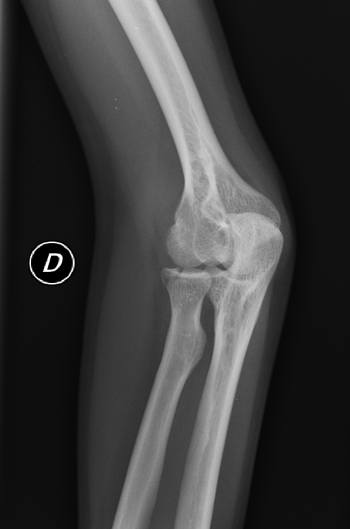

En RX simple no se aprecian claras líneas de fractura (figura 1 y figura 2), y ante la duda se decide realizar proyecciones adicionales para intentar despejar cabeza de radio. Se realizan dos proyecciones adicionales: oblicua de codo (oblicuando todo el cuerpo del paciente, para no movilizar el codo por dolor), y perfil de codo angulado el tubo caudalmente entre 10-15 grados. En ambas proyecciones se visualiza una clara fractura del mismo (figura 3 y figura 4).

(figura 2)